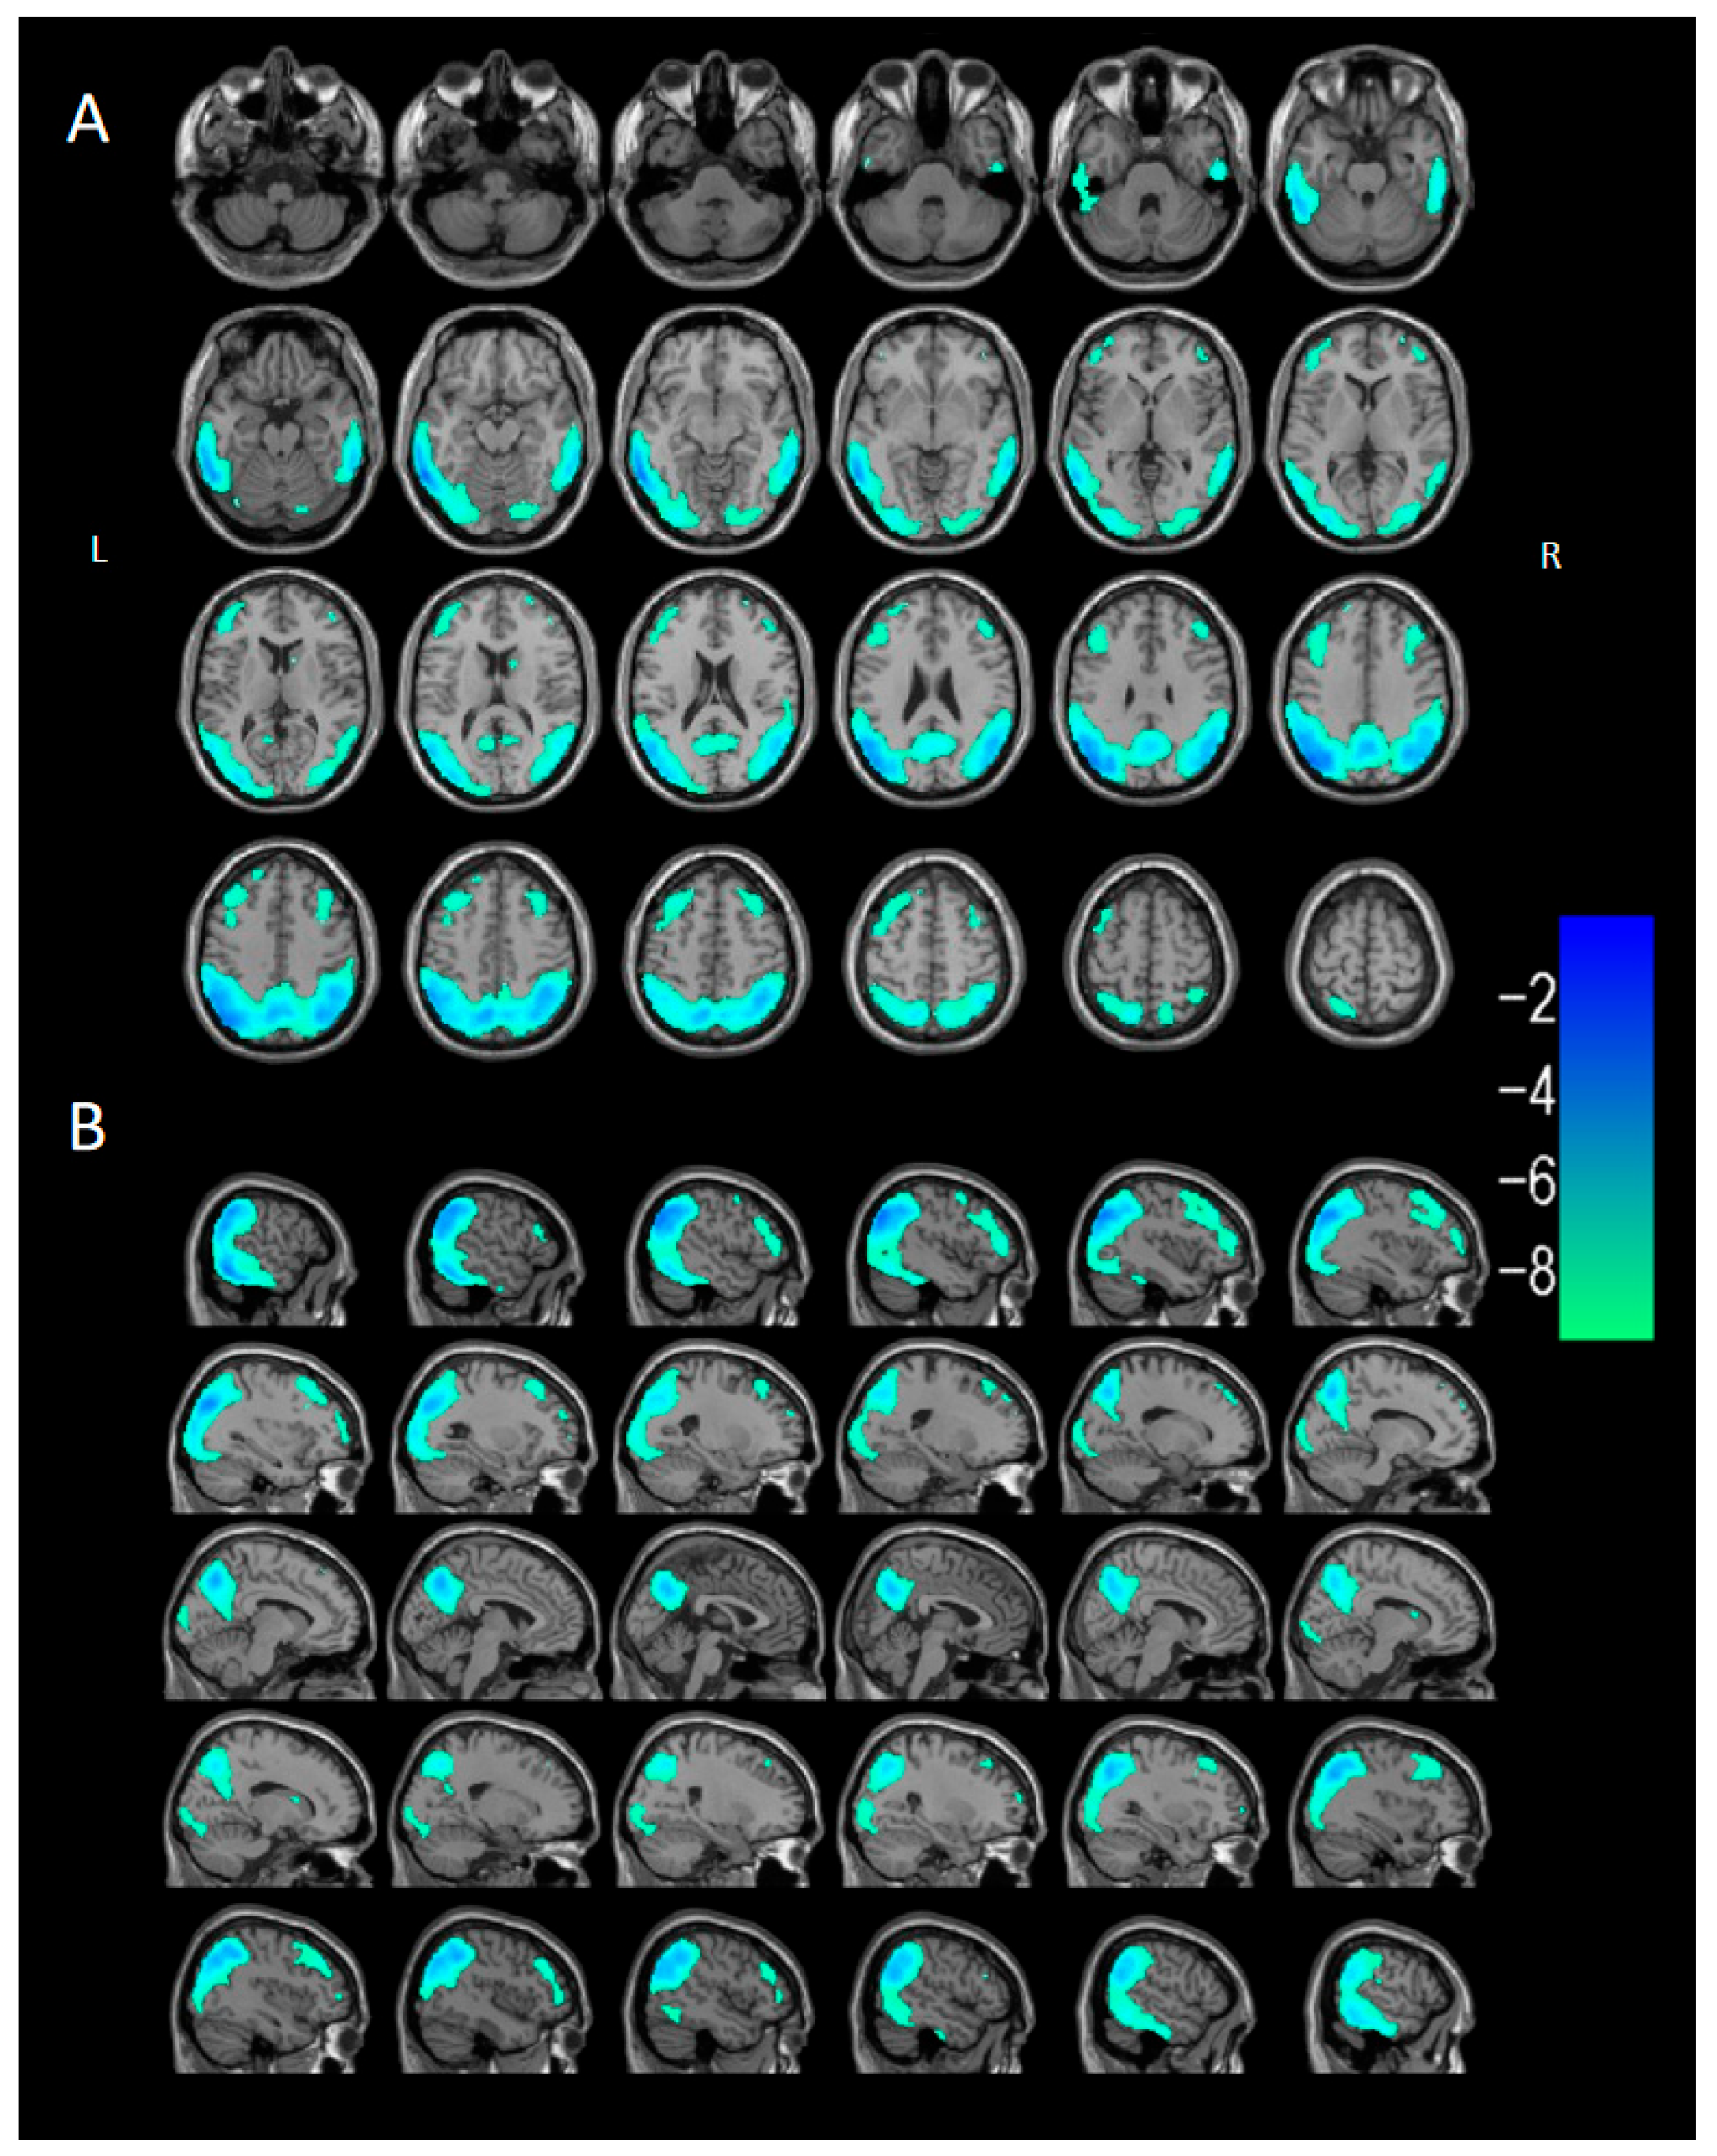

3.2.3. Voxel-Based Semi-Quantitative Analysis

| Brain Region of Cluster | Cluster Size (Voxels) | Peak t | Peak MNI Coordinates | ||

| DLB < HC | |||||

| Cluster 1 | 29,280 | −11.5121 | −44 | −74 | 36 |

| Occipital_Mid_L (aal) | 2736 | ||||

| Temporal_Mid_L (aal) | 2409 | ||||

| Parietal_Inf_L (aal) | 1864 | ||||

| Temporal_Mid_R (aal) | 1836 | ||||

| Precuneus_L (aal) | 1653 | ||||

| Precuneus_R (aal) | 1609 | ||||

| Temporal_Inf_L (aal) | 1536 | ||||

| Occipital_Mid_R (aal) | 1460 | ||||

| Angular_R (aal) | 1460 | ||||

| Temporal_Inf_R (aal) | 1337 | ||||

| Parietal_Sup_L (aal) | 1167 | ||||

| Angular_L (aal) | 1104 | ||||

| Parietal_Inf_R (aal) | 1056 | ||||

| SupraMarginal_R (aal) | 847 | ||||

| Parietal_Sup_R (aal) | 814 | ||||

| Occipital_Inf_L (aal) | 701 | ||||

| Occipital_Sup_L (aal) | 669 | ||||

| SupraMarginal_L (aal) | 656 | ||||

| Occipital_Sup_R (aal) | 491 | ||||

| Fusiform_L (aal) | 479 | ||||

| Cuneus_L (aal) | 402 | ||||

| Cuneus_R (aal) | 279 | ||||

| Occipital_Inf_R (aal) | 234 | ||||

| Temporal_Sup_R (aal) | 216 | ||||

| Calcarine_R (aal) | 194 | ||||

| Lingual_R (aal) | 185 | ||||

| Lingual_L (aal) | 147 | ||||

| Calcarine_L (aal) | 136 | ||||

| Temporal_Sup_L (aal) | 128 | ||||

| Cingulum_Post_L (aal) | 70 | ||||

| Cingulum_Post_R (aal) | 33 | ||||

| Cluster 2 | 1037 | −6.4095 | 42 | 32 | 38 |

| Frontal_Mid_R (aal) | 908 | ||||

| Frontal_Inf_Tri_R (aal) | 57 | ||||

| Cluster 3 | 2379 | −6.5266 | −32 | 24 | 52 |

| Frontal_Mid_L (aal) | 1628 | ||||

| Frontal_Inf_Tri_L (aal) | 473 | ||||

| Frontal_Sup_L (aal) | 104 | ||||